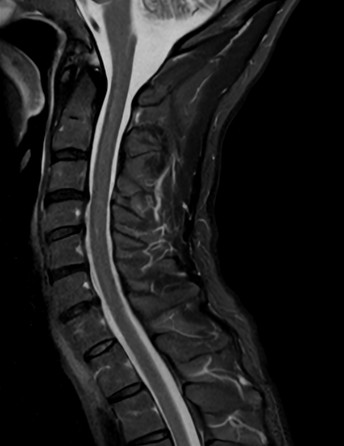

High quality Cervical Spine imaging with SmartSpeed Precise